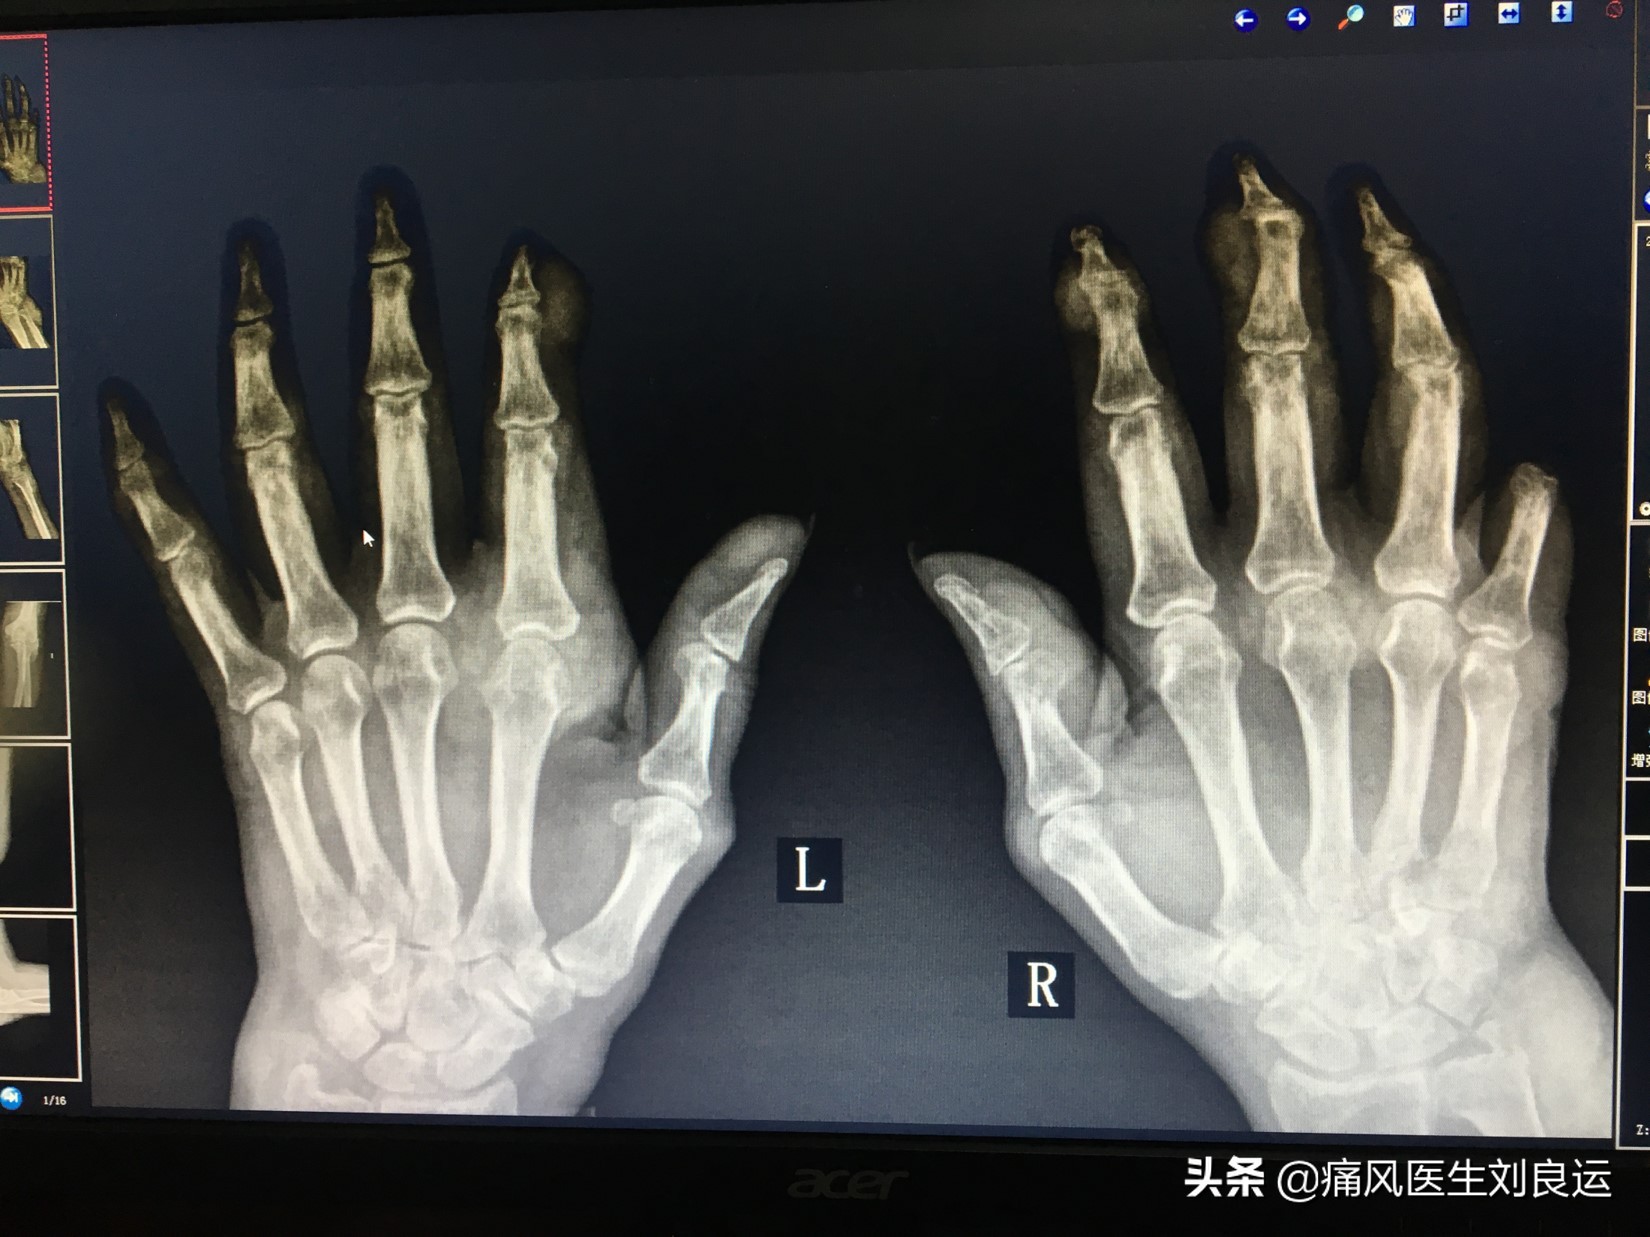

X线下双手痛风石

检查:根据患者病情需要于当天安排住院治疗,期间检查尿酸511.4umol/L;血常规、肝功能、肾功能、葡萄糖、凝血未见异常;腹部彩超显示双肾尿盐结晶沉积;DR左手多关节痛风石伴骨质轻微破坏。